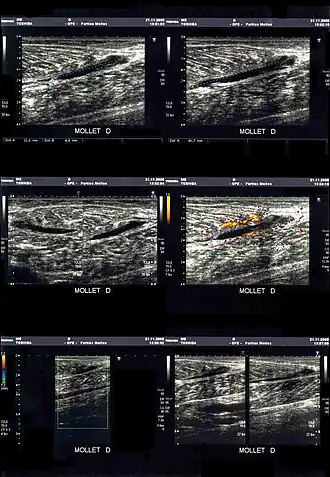

La déchirure apparait sous la forme d'une zone hypoéchogène (sans écho, et donc noire).

En cas de doute ou pour préciser les dégâts musculaires dans les cas les plus graves, une déchirure peut être mise en évidence par l'imagerie médicale[15] :

- échographie/échotomographie : « examen le plus utile et le moins cher, permet une étude des fibres musculaires, des tendons et des aponévroses. Ses limitations sont la mauvaise analyse des zones profondes, comme l’insertion proximale des ischio-jambiers, et la difficulté à détecter parfois les cicatrices »[3].

- IRM : plus coûteuse, elle est aussi plus sensible, sans toutefois permettre d’étudier directement les fibres musculaires[16]. Elle est utilisée en cas d'insuffisance de diagnostic par échographie (en deuxième intention)[3].